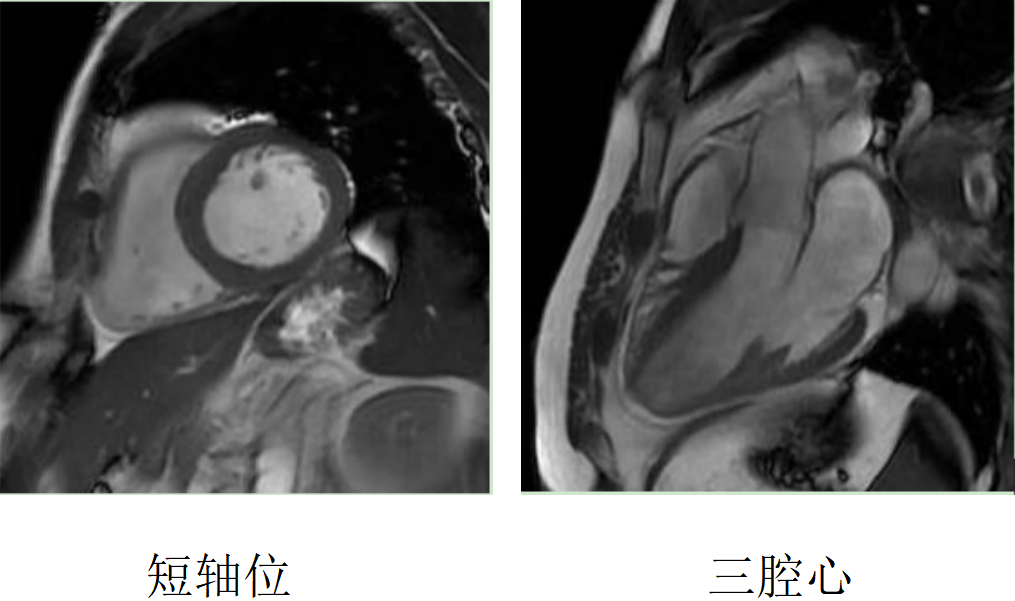

心臟磁共振被稱為心臟“一站式”檢查,通過多參數成像能夠對心臟的結構、功能、室壁運動、心臟瓣膜、心肌灌注和活性進行“一站式”評估。主要通過電影序列(短軸、兩腔心、四腔心、三腔心)、T2WI序列、首過灌注序列以及延遲強化序列對心臟進行綜合成像。